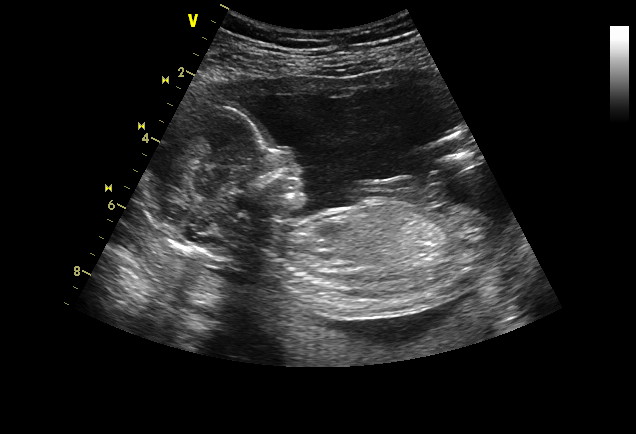

Holky, taky gratuluji k fajnovým výsledkům :) Mám úsměv na tváři, když už vím, co to bude, je to zase o něco víc osobitější :) Posílám foto